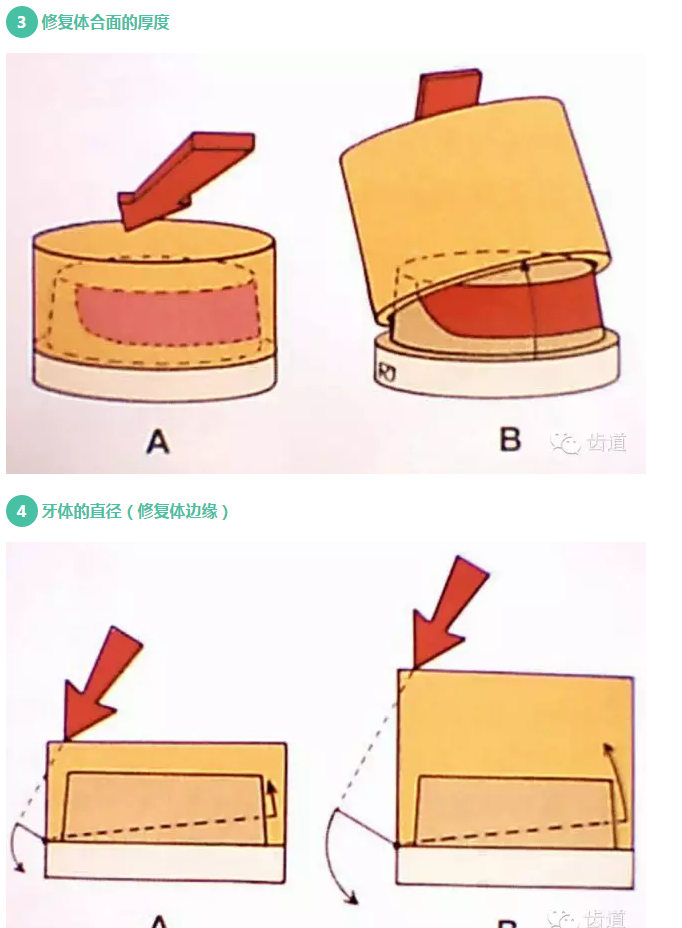

l預留修復體的空間

牙的外形及洞形的幾何形狀:主要是牙體制備出一定聚合角度產(chǎn)生的阻擋作用